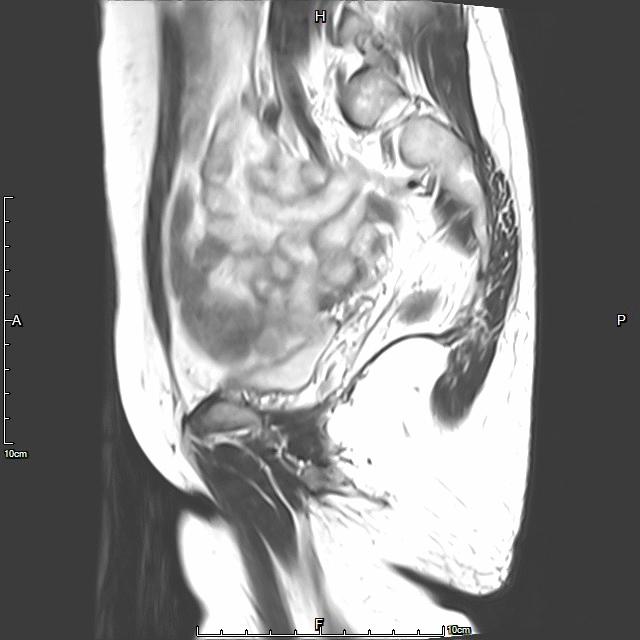

中年患者,患有“子宫腺肌瘤”7年余,长期受痛经、月经量增多折磨,严重影响生活质量。经多处求医,经历药物调理、“曼月乐”宫腔植入、“海扶刀”消融术等多种治疗,痛经、月经量多等情况一直无法得到有效缓解,病情日益严重。

- 术前MRI检查显示子宫明显增大。

术前MRI检查显示子宫明显增大

术后复查MRI显示子宫明显缩小,腺肌瘤明显坏死吸收